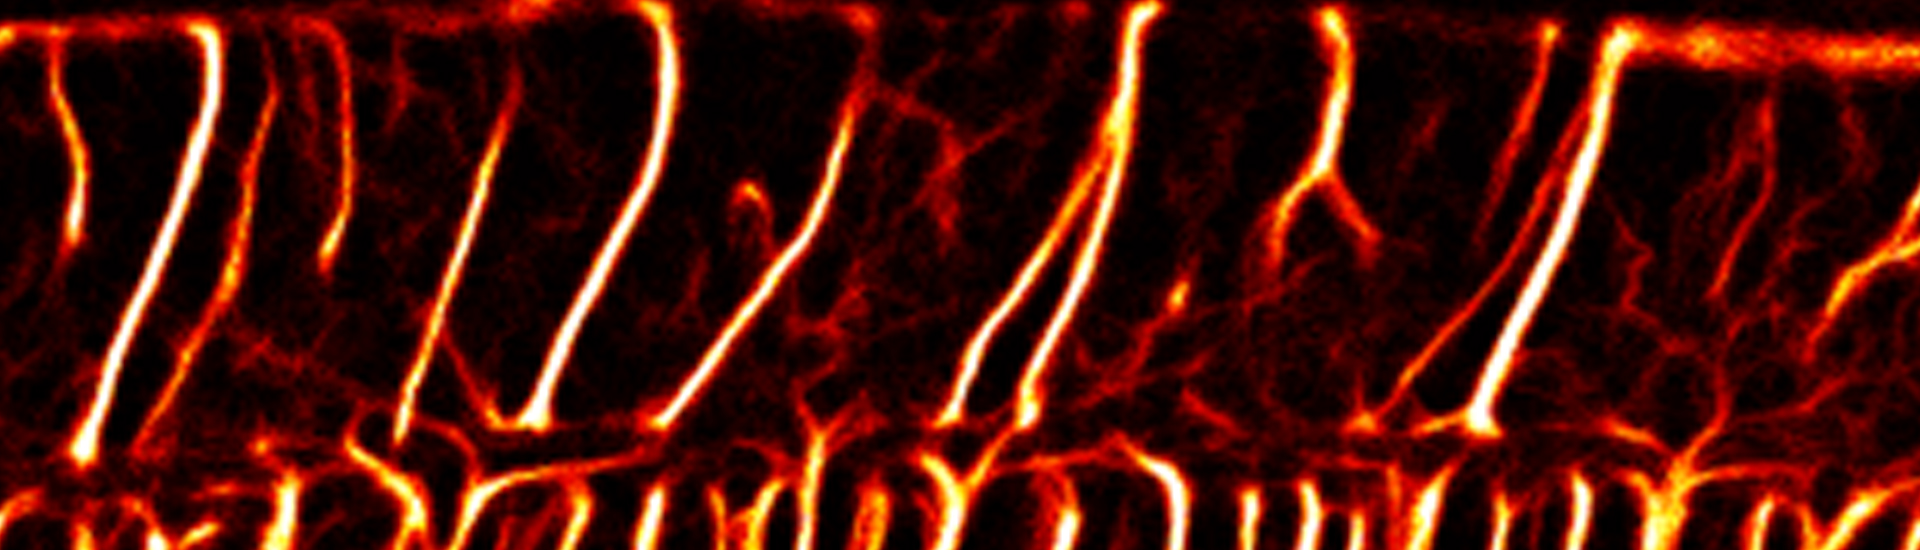

Although the aging brain is studied quite extensively, there are very few studies examining how the spinal cord tissue and its vasculature changes with age. Our group is the first to examine the aged spinal cord and alterations in intraspinal vasculature with unprecedented temporal and spatial resolutions using intravital ultrasound imaging.